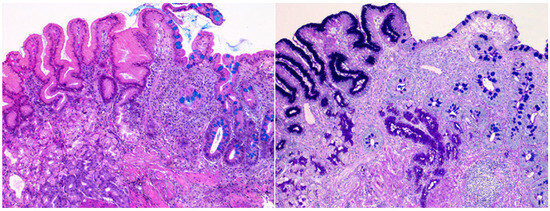

2.4. Histopathological Assessment